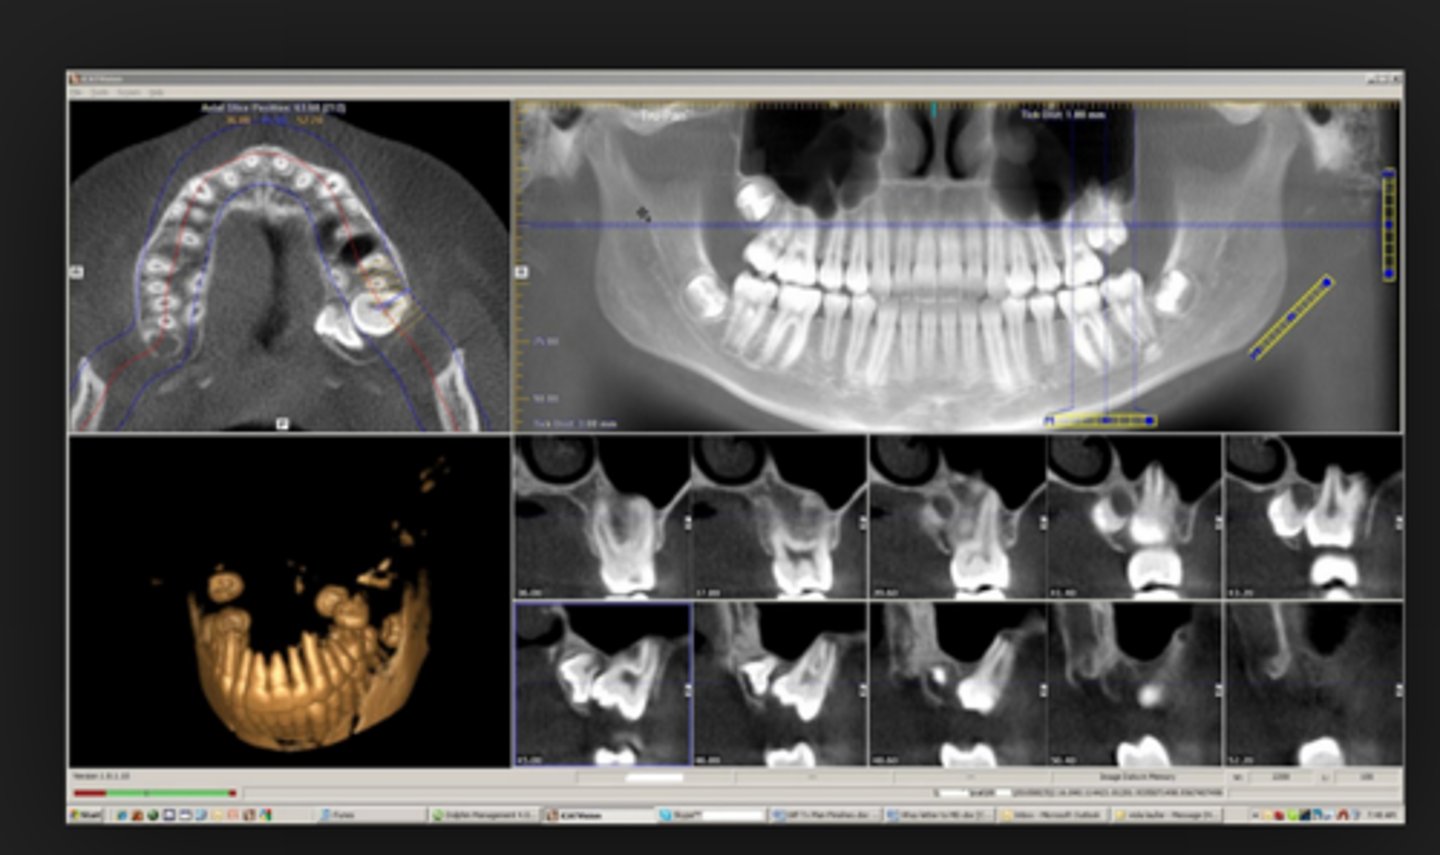

Cone - Beamed Computed Tomography (CBCT)

what type of x-ray is this ?

what does a CBCT x-ray show?

a 3D image of the dental structures, soft tissues, nerve pathways, and sinuses

what is the primary purpose a CBCT x-ray?

IMPLANT PLANNING, ROOT CANALS, ORTHODONTICS, ORAL ISSUES

what are the other purposes of a CBCT x-ray?

- to see bone depth and nerve locations

- evaluating jaw joint issues

what is unique about CBCT x-rays?

they produce the HIGHEST radiation dose but offers the most detailed spatial information (3D)